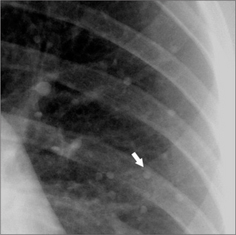

image

Figure 21.7 Multiple small–very small–calcified nodules were present in the mid and upper zones of both lungs. One of the nodules is indicated by the arrow. Previous chickenpox pneumonia.